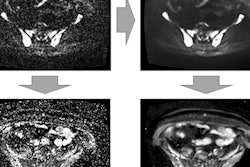

DWI can detect, characterize, and evaluate the movement of water molecules at the extracellular space; the presence of biological membranes hinders the free movement of water molecules. DWI is usually based on a single-shot echo-planar imaging sequence applying two motion-probing gradients, separated by a short lapse of time, that allow one to determine the displacement of water molecules between them, they stated.

Apparent diffusion coefficient (ADC) is the parameter that helps quantify the degree of water molecules displaced, and depending on the combination of DWI signal intensity and ADC values, different biological interpretations about tissues features can be performed.

"There is an inherent inhomogeneity of magnetic field in the MSK system due to the presence of multiple air-bone-fat-soft tissue interfaces," they continued. "The acquisition of DWI may need some specific technical adjustment in order to try to minimize the possible artifacts and maximize the signal-to-noise ratio."